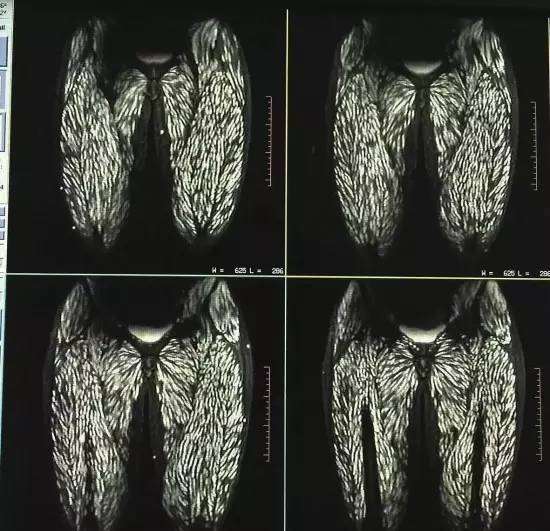

生食には寄生虫のリスクがついてまわるものだが、中国ではこのたび、生のブタ肉を食べ続けてきた女性が、全身寄生虫に侵されていたことが判明し、医師を驚かせた。原因不明の痛みが発症したことから明らかになったという。

病院では頭部MRIと全身CTスキャンが行われたが、その検査結果は専門家さえも驚く衝撃的なものだった。それもそのはず、女性の全身はすでに無数の寄生虫に侵されており、大脳や顔面の筋肉にさえも感染が見られるひどい有様だったからだ。